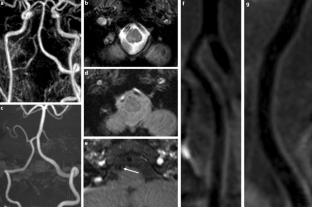

The HR-MRI findings were classified into complete normalization (normal lumen and wall with or without mild enhancement, n = 6), complete normalization with minimal wall changes (focal wall thickening with enhancement but normal luminal angiography, n = 8), incomplete normalization (focal wall thickening with enhancement with dilatation and stenosis on luminal angiography, n = 4), dissecting aneurysm (fusiform aneurysm with residual dissection findings, n = 8) and occlusion (small outer arterial diameter with diffuse contrast enhancement, n = 3).

The use of HR-MRI can demonstrate the distinguishing morphological features of chronic stage of spontaneous and unruptured ICAD as complete normalization, complete normalization with minimal wall changes, incomplete normalization, dissecting aneurysm and occlusion.